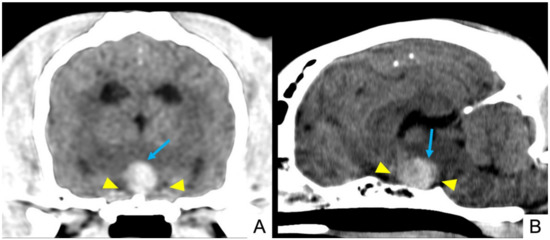

3.4. Imaging Findings